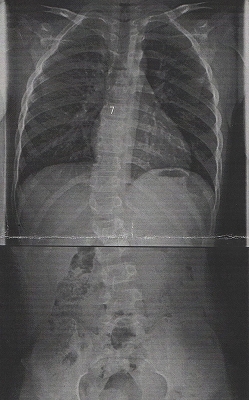

20170809改善後レントゲン

平成29年7月21日:治療後(5回目)

0度